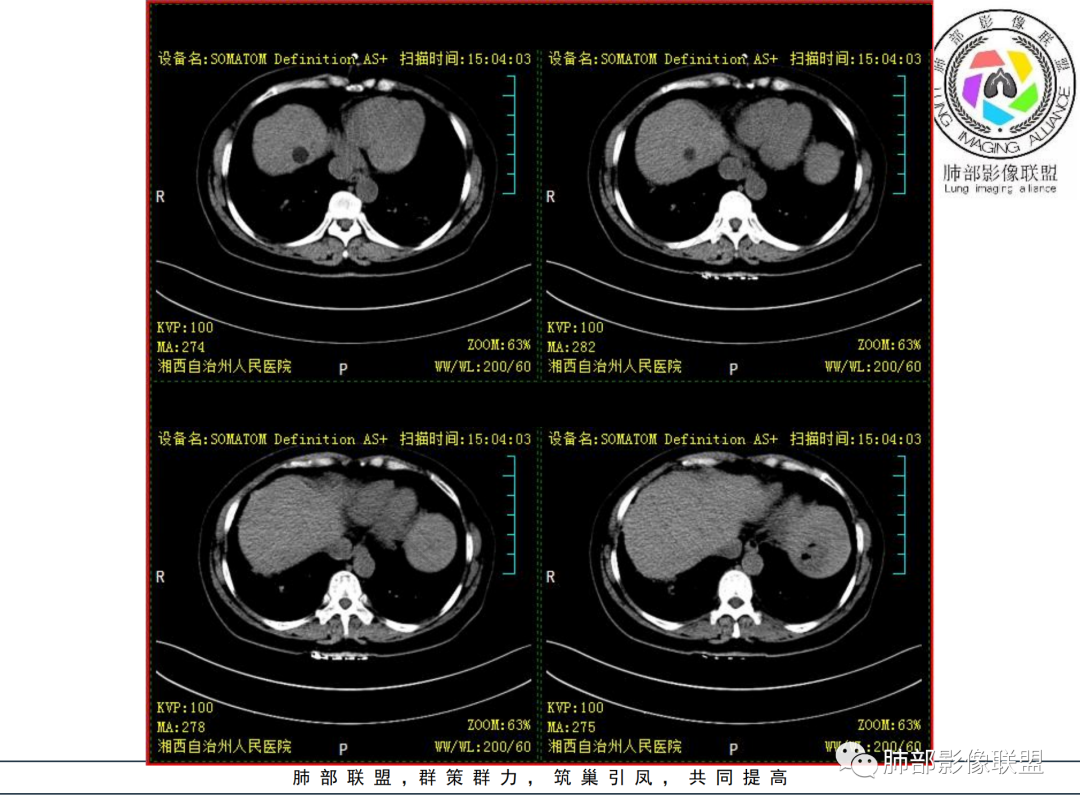

中年女性,既往类风湿,症状逍遥复查胸CT提示双肺结节较前扩大。无发热,无感染中毒症状。

胸部CT提示双肺多发的斑片实变结节影,磨玻璃。病灶分布以双肺胸膜下为主,部分病灶以支气管血管素分布,病灶内可见支气管穿行。总体符合间质性肺疾病。

荚膜抗原阴性结核阴性,肺泡灌洗液回报无特异性,无感染中毒症状以及血象异常,暂不考虑感染。

肿瘤也不符合。

考虑间质性肺疾病,机化性肺炎,